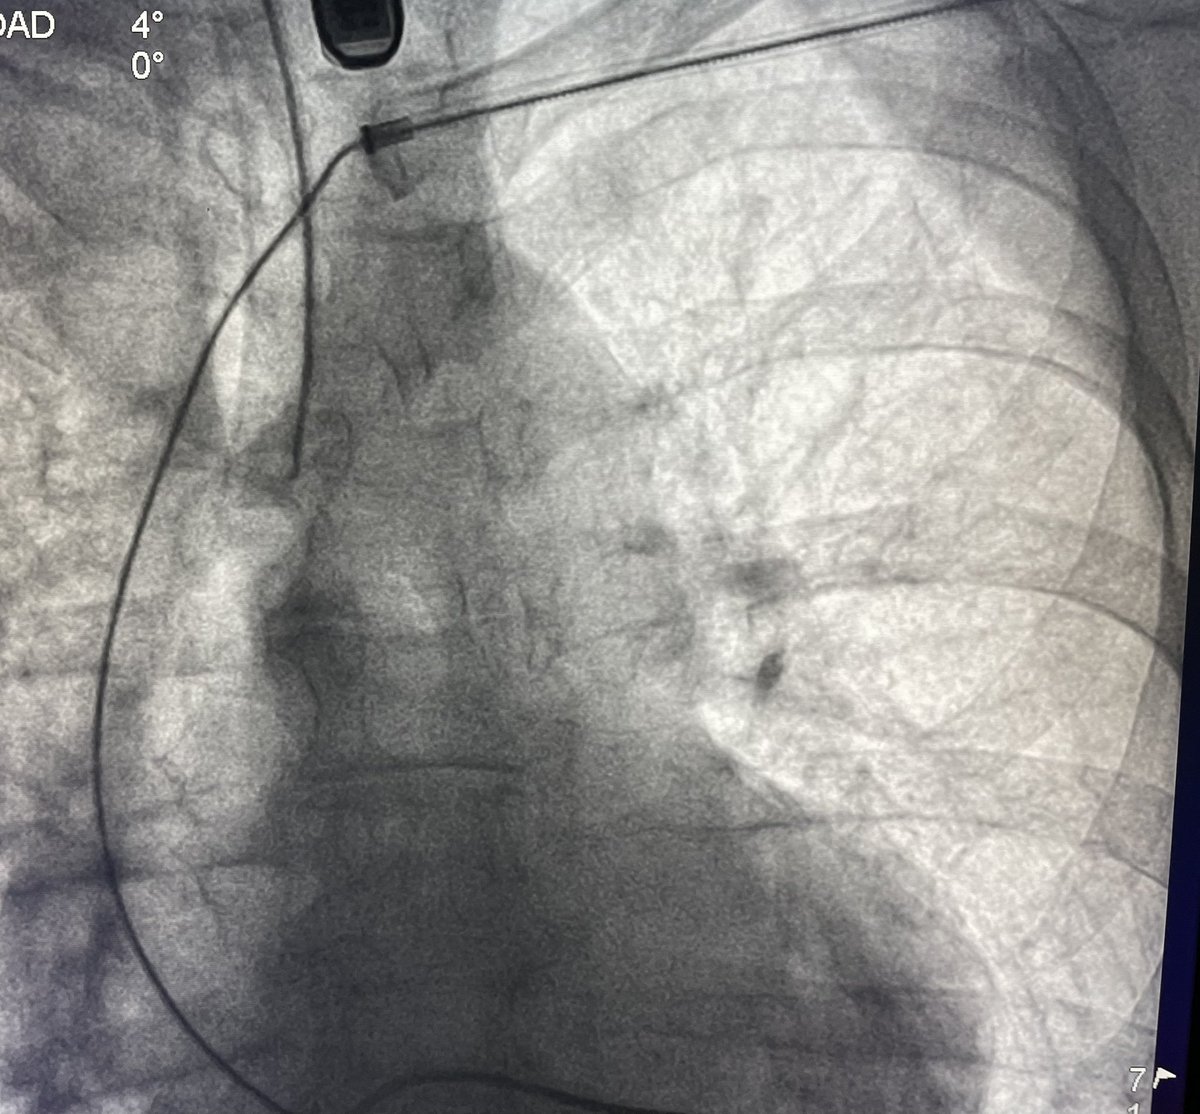

Great PVC case today. One burn and gone. Male, 30% PVC burden, EF 42%. Thanks to @ignespinozac for the map. @DrRoderickTung @hhuang123 @andresenriqueza @FellowEP

Parahisian PVC, always a challenge to ablate arrhythmias in this region. “We aware of your neighbors @DrFerminGarcia used to say”. Ablated from RCC. @andresenriqueza @FellowEP @DrRoderickTung @hhuang123